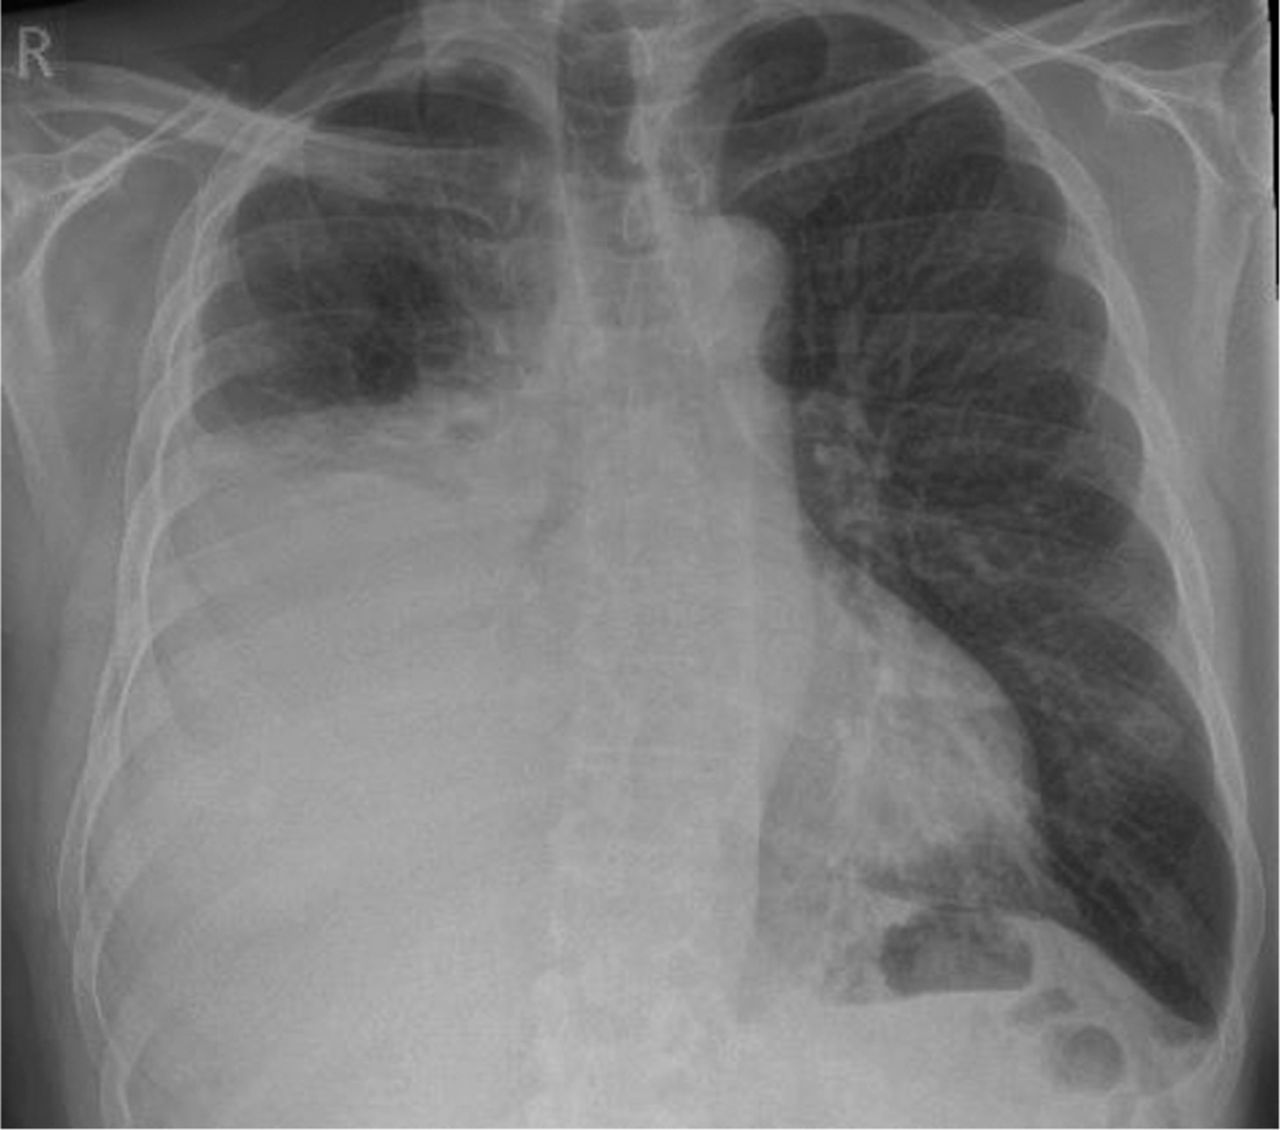

Los derrames pleurales se refieren a la acumulación anormal de líquido en el espacio pleural, que es la cavidad que rodea los pulmones dentro de la cavidad torácica. La presencia de líquido en esta área puede deberse a diversas causas y procesos fisiopatológicos. La mayoría de los derrames pleurales están relacionados con cinco procesos principales: